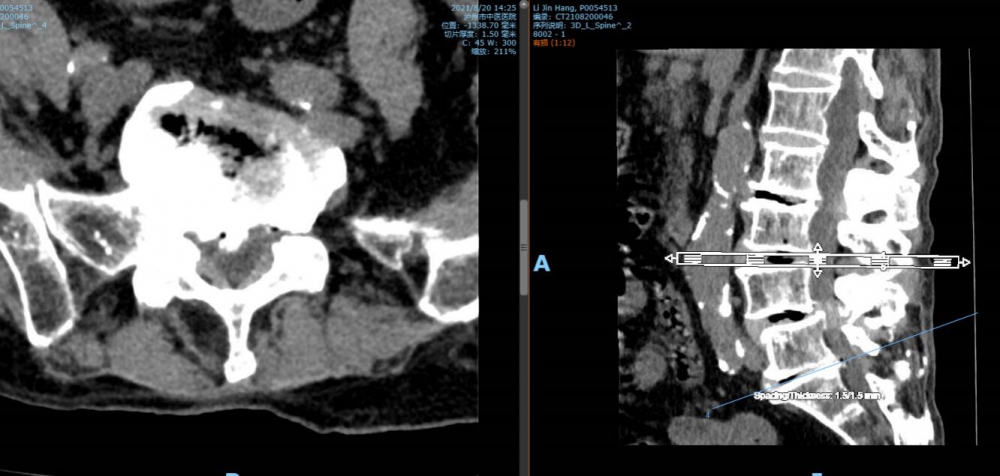

5 骶1椎間盤CT